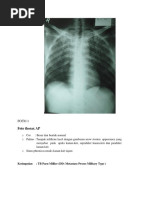

YTH TS :

Hasil pemeriksaan Thorax PA:

- Corakan bronchovascular normal

- Tidak tampak proses spesifik aktif dan lesi –lesi noduler kedua paru

- COR : CTI dalam batas normal, Aorta normal

- Kedua sinus dan diafragma baik

- Tulang-tulang intak

Kesan : Foto Thorax dalam Batas Normal